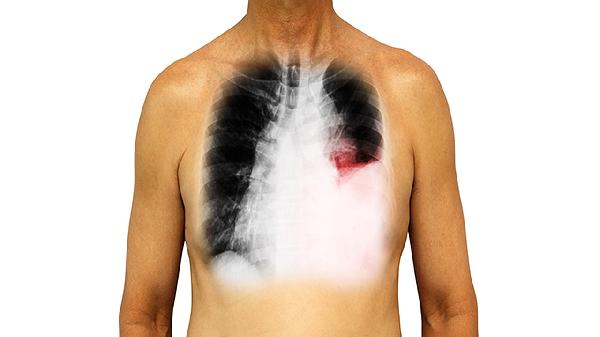

2、影像特征:肺结节在CT或X光片上表现为清晰的圆形或类圆形病灶,密度均匀或不均匀;肺结节影可能表现为模糊的阴影,边界不清,密度不均。

肺结节与肺结节影并不是完全相同的概念,两者在影像学表现和临床意义上存在一定差异。肺结节通常指肺部实质性的圆形或类圆形病灶,直径小于3厘米,可能是良性或恶性病变。肺结节影则更广泛,包括肺部影像学上显示的任何结节样阴影,可能由多种原因引起,如炎症、感染、肿瘤等。诊断肺结节或肺结节影时,医生会根据影像学特征、患者病史和辅助检查结果进行综合判断。